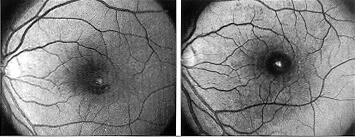

黄斑前膜